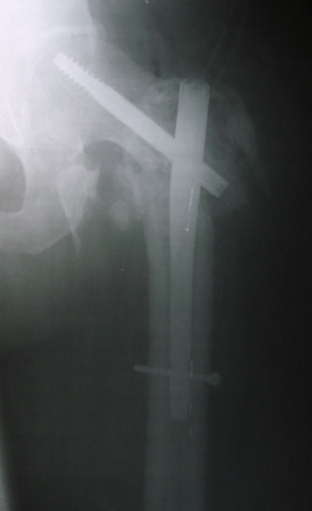

Уважаемые коллеги! На консультацию пришел больной 44-х лет (снимки 1 и 2): упал на улице 26.11.2012г., оперирован в одном из лечебных учреждений 26.11.2012. Сделали контрольные рентгенограммы и КТ. Хотели-бы обсудить варианты оперативного лечения: DHS или БИОС?

Если честно, то на первом снимке отломки "стояли" лучше, чем после "репозиции" и остеосинтеза пресловутой Г-образной пластиной-не восстановлена дуга Адамса, ну или по другому- отсутствие медиальной опоры. По этой же причине не рекомендую DHS, только штифт типа Гамма, при этом обязательно

восстановить шеечно-диафизарный угол, а клинок установить максимально близко к дуге Адамса, до субходральной зоны головки бедр. кости.

DHS в этом случае не показан, так как перелом из чрезвертельного чудесным образом превратился в подвертельный (А 3 по классификации АО). На мой взгляд, можно рассматривать 2 варианта:

1.Пластины. 95-градусная мыщелковая пластина. Корректно введённый в проксимальную часть клинок позволяет относительно легко выполнить репозицию, манипулируя диафизарной частью пластины. Несмотря на то, что имплантат старый, эта операция до сих пор нередко практикуется даже в продвинутых зарубежных клиниках в подобных случаях. Это может в силу разных причин не получиться. Хорошо бы иметь в запасе на всякий случай какую-нибудь пластину с угловой стабильностью (хотя бы DF на другую ногу, его можно перевернуть и установить проксимально).

2. Альтернатива - любой гвоздь гамма-конфигурации. Но репозиция - открытая.

Спасибо всем, кто оказывал практическую помощь в принятии решения. Сегодня сделали операцию. Снимки интраоперационные, аксиальный не "публикую" еле видно.

Поверьте на слово - стержень прошел через центр шейки, в обоих плоскостях. Других вариантов не было из-за следов предшествующего вмешательства. Хотели-бы обсудить результат в свете послеоперационного ведения (какую разрешать активность, в какие сроки).